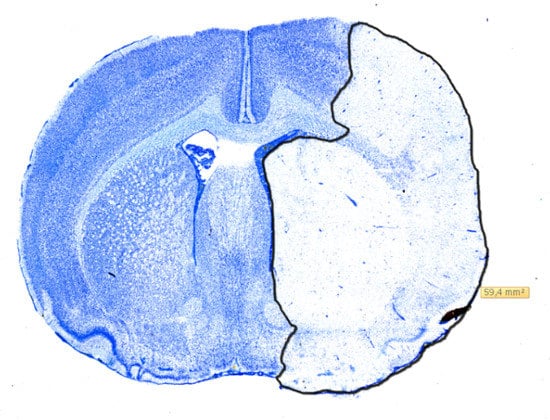

2.3. Histology

4.4. Infarct Volumetry